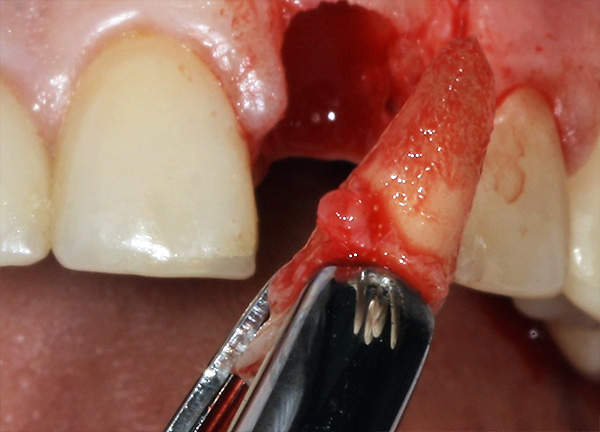

A remoção mais não traumática da raiz com a preservação das gengivas e paredes ósseas do buraco é realizada: